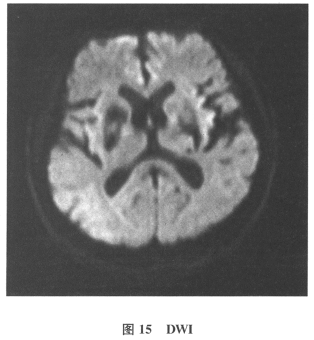

[多选题]患者男,61岁。因“发作性头晕2年,加重伴记忆力下降、走路不稳3月余”就诊。查体:BP140/70mmHg;意识清楚,构音障碍,近期记忆力及远期记忆力

[单选题]患者男,61岁。因“发作性头晕2年,加重伴记忆力下降、走路不稳3月余”就诊。查体:BP140/70mmHg;意识清楚,构音障碍,近期记忆力及远期记忆力